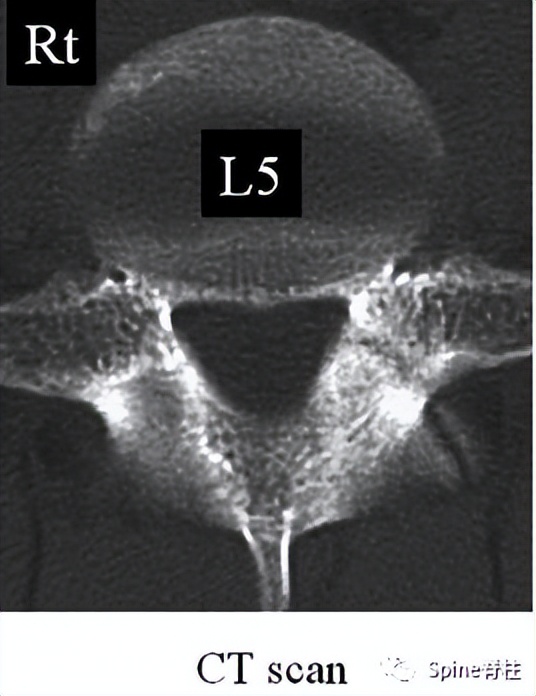

2. 腰椎峡部和峡部裂在CT片上的表现

峡部裂的CT分型 :A=早期(线性骨折),B=进展期(明显的骨间隙),C=终末期(假关节形成)

右侧为进展期峡部裂,左侧为早期峡部裂,右侧图片是支具固定7个月后愈合